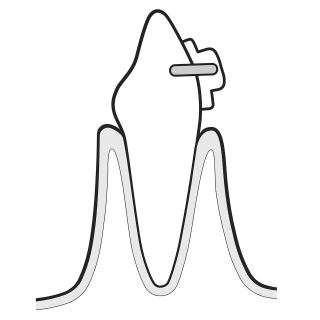

06 PIEZON® PS

Remove remaining calculus:

- Use the minimally invasive EMS PS instrument supra-and sugingivally up to 10 mm

- Clean > 10 mm pockets with mini curette

- Use EMS PI Instrument around implants up to 3 mm subgingivally and on restorations

TREAT GINGIVITIS

AIRFLOW® PLUS Powder easily and safely removes biofilm and early calculus from coronal surfaces and sulcus. The PIEZON® PS NO PAIN Instrument removes the remaining calculus in a minimally invasive way.